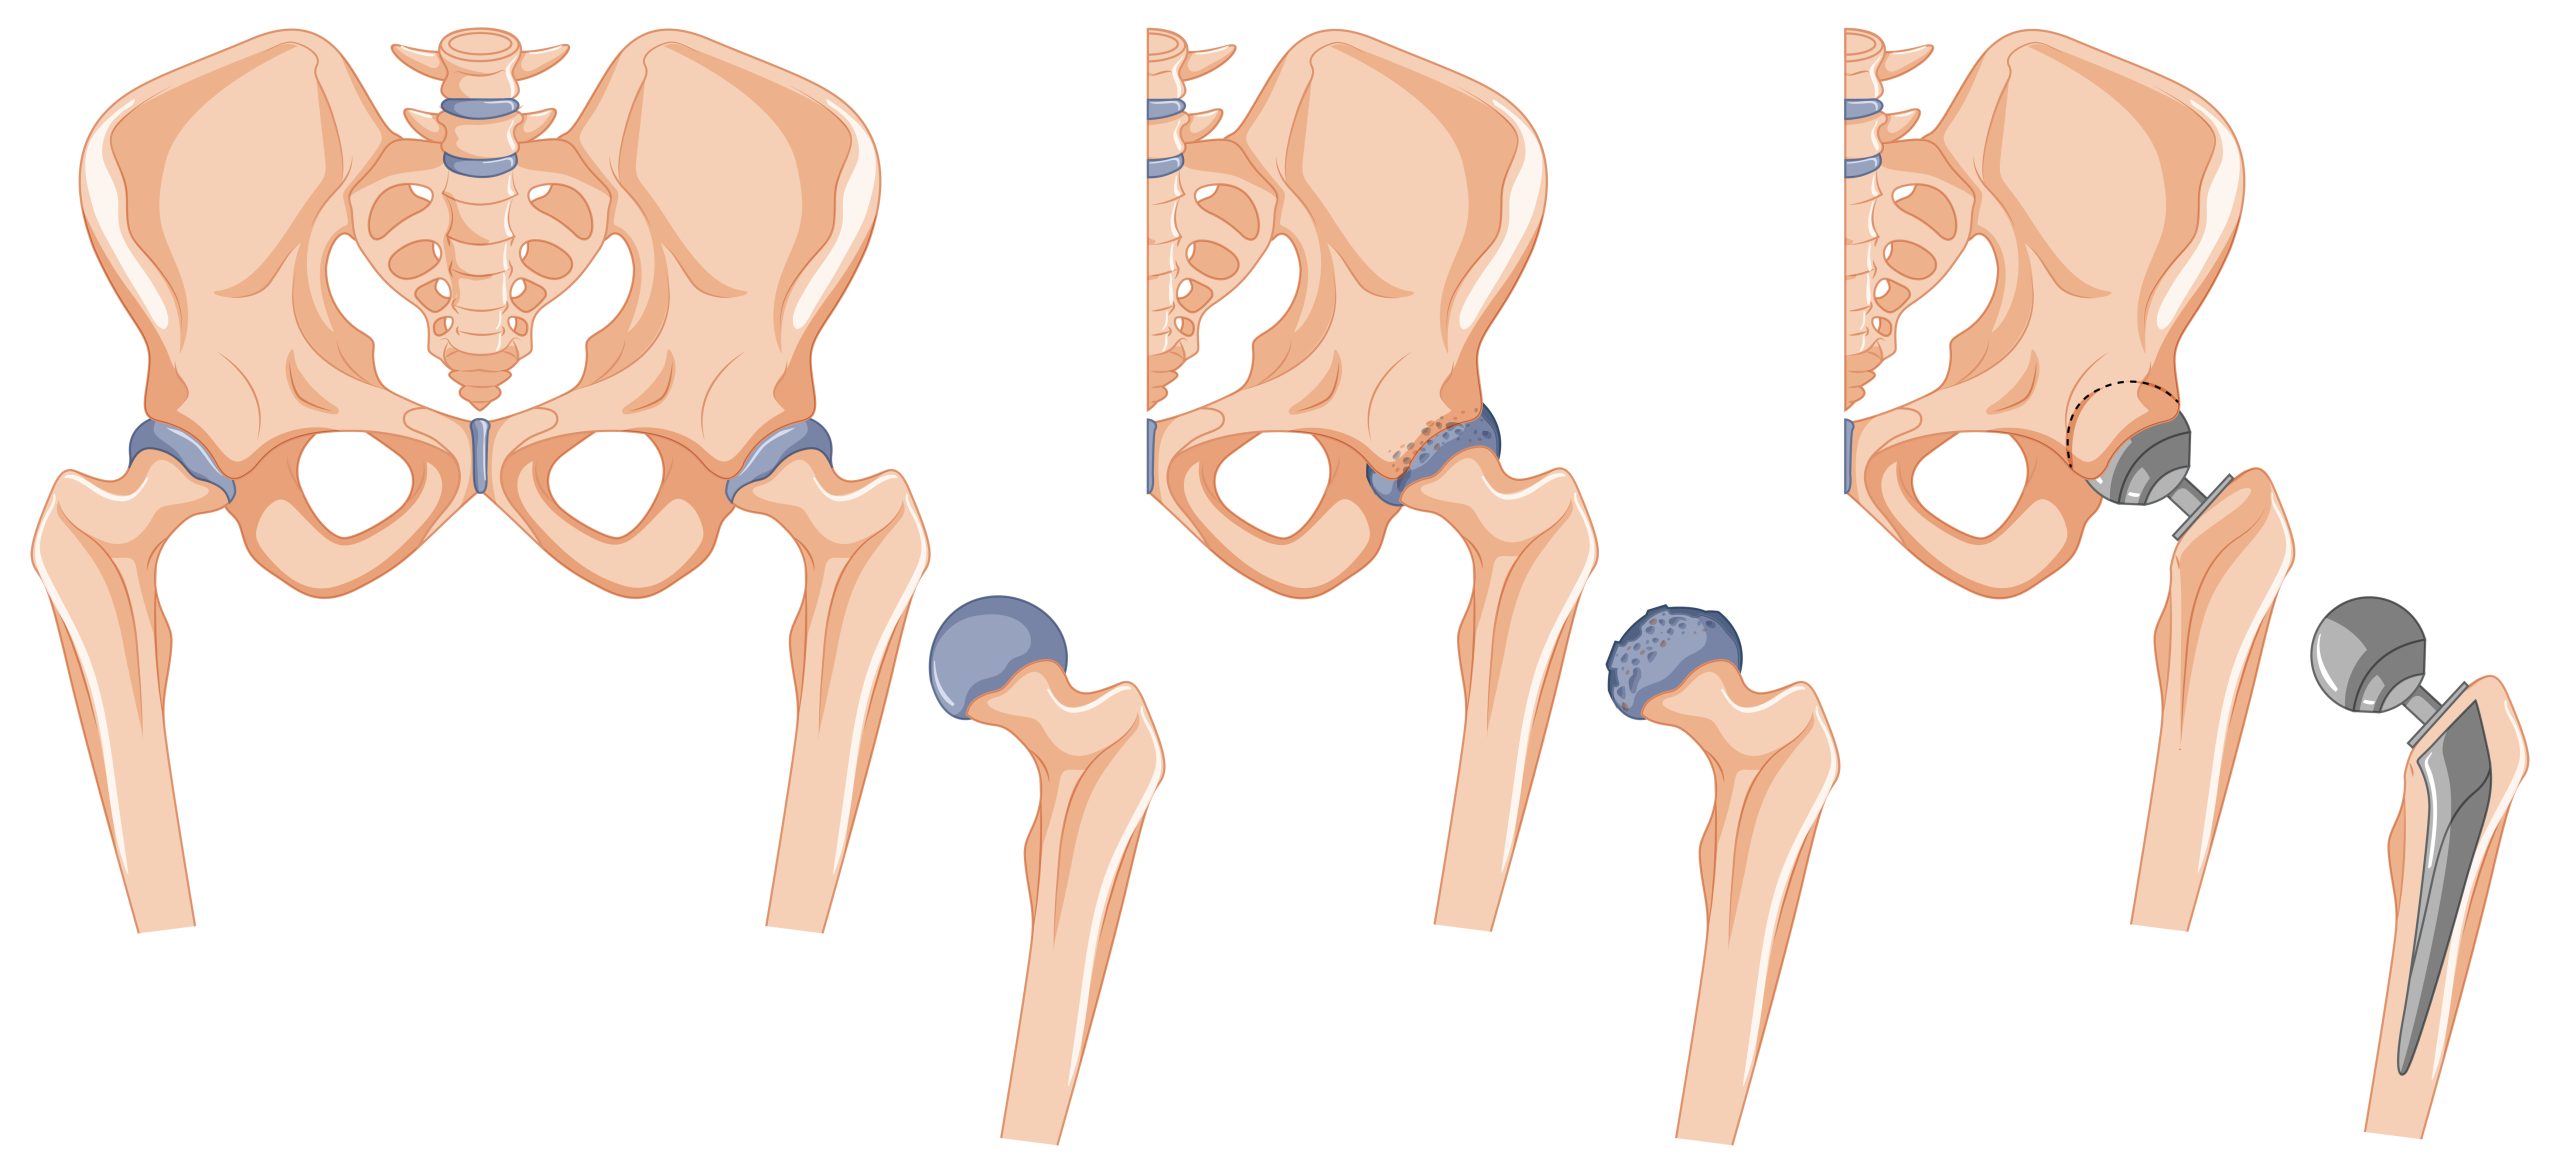

The procedure involves removing the damaged or diseased parts of the hip joint and replacing them with prosthetic components made of metal, plastic, or ceramic. This artificial joint performs the natural function of the hip, providing improved mobility and pain relief.